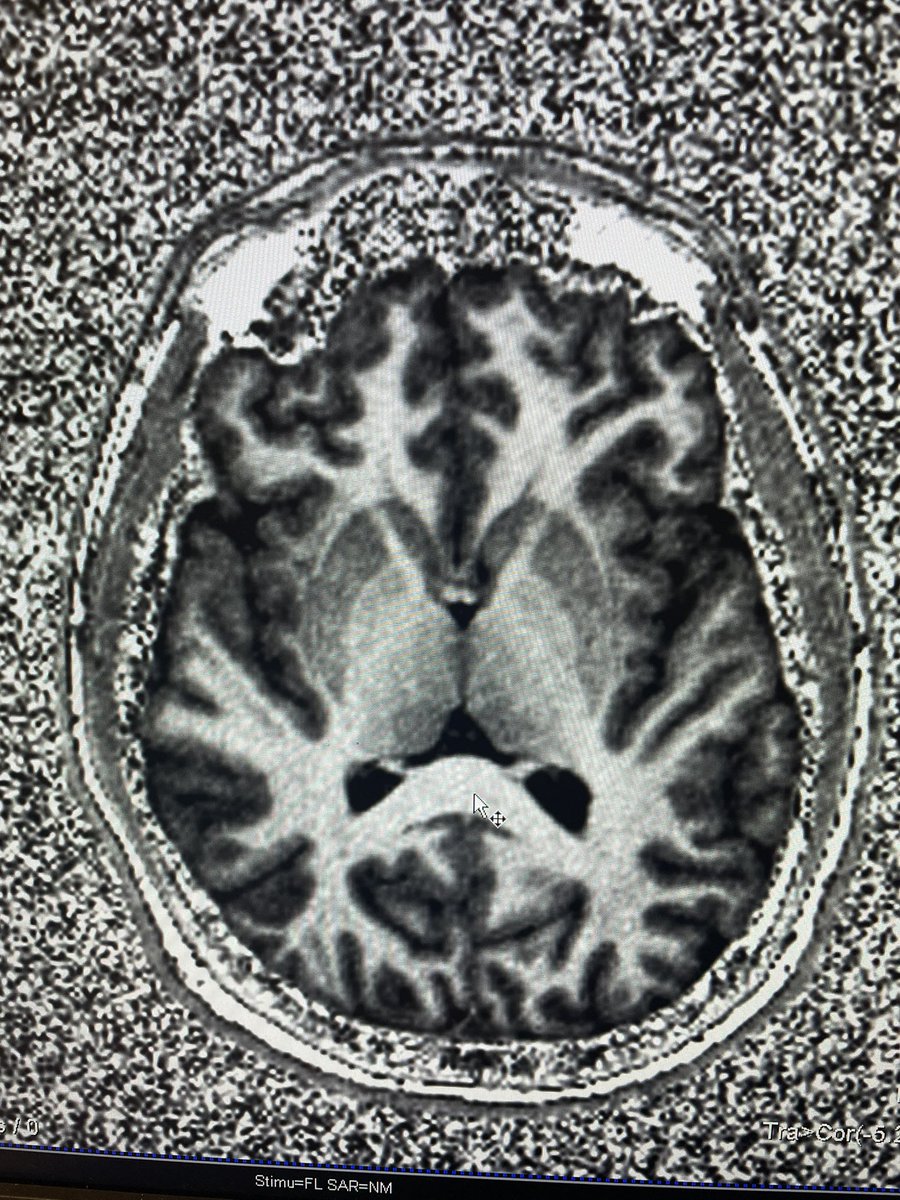

Join us for on Sunday at ASSFN in Nashville, TN for a Medtronic-sponsored lunch symposium on the latest updates in technique and patient selection in LITT for epileptic foci! Sunday, June 2 from 12:00 – 12:55pm. #Visualase #LITT @JTWillieMD